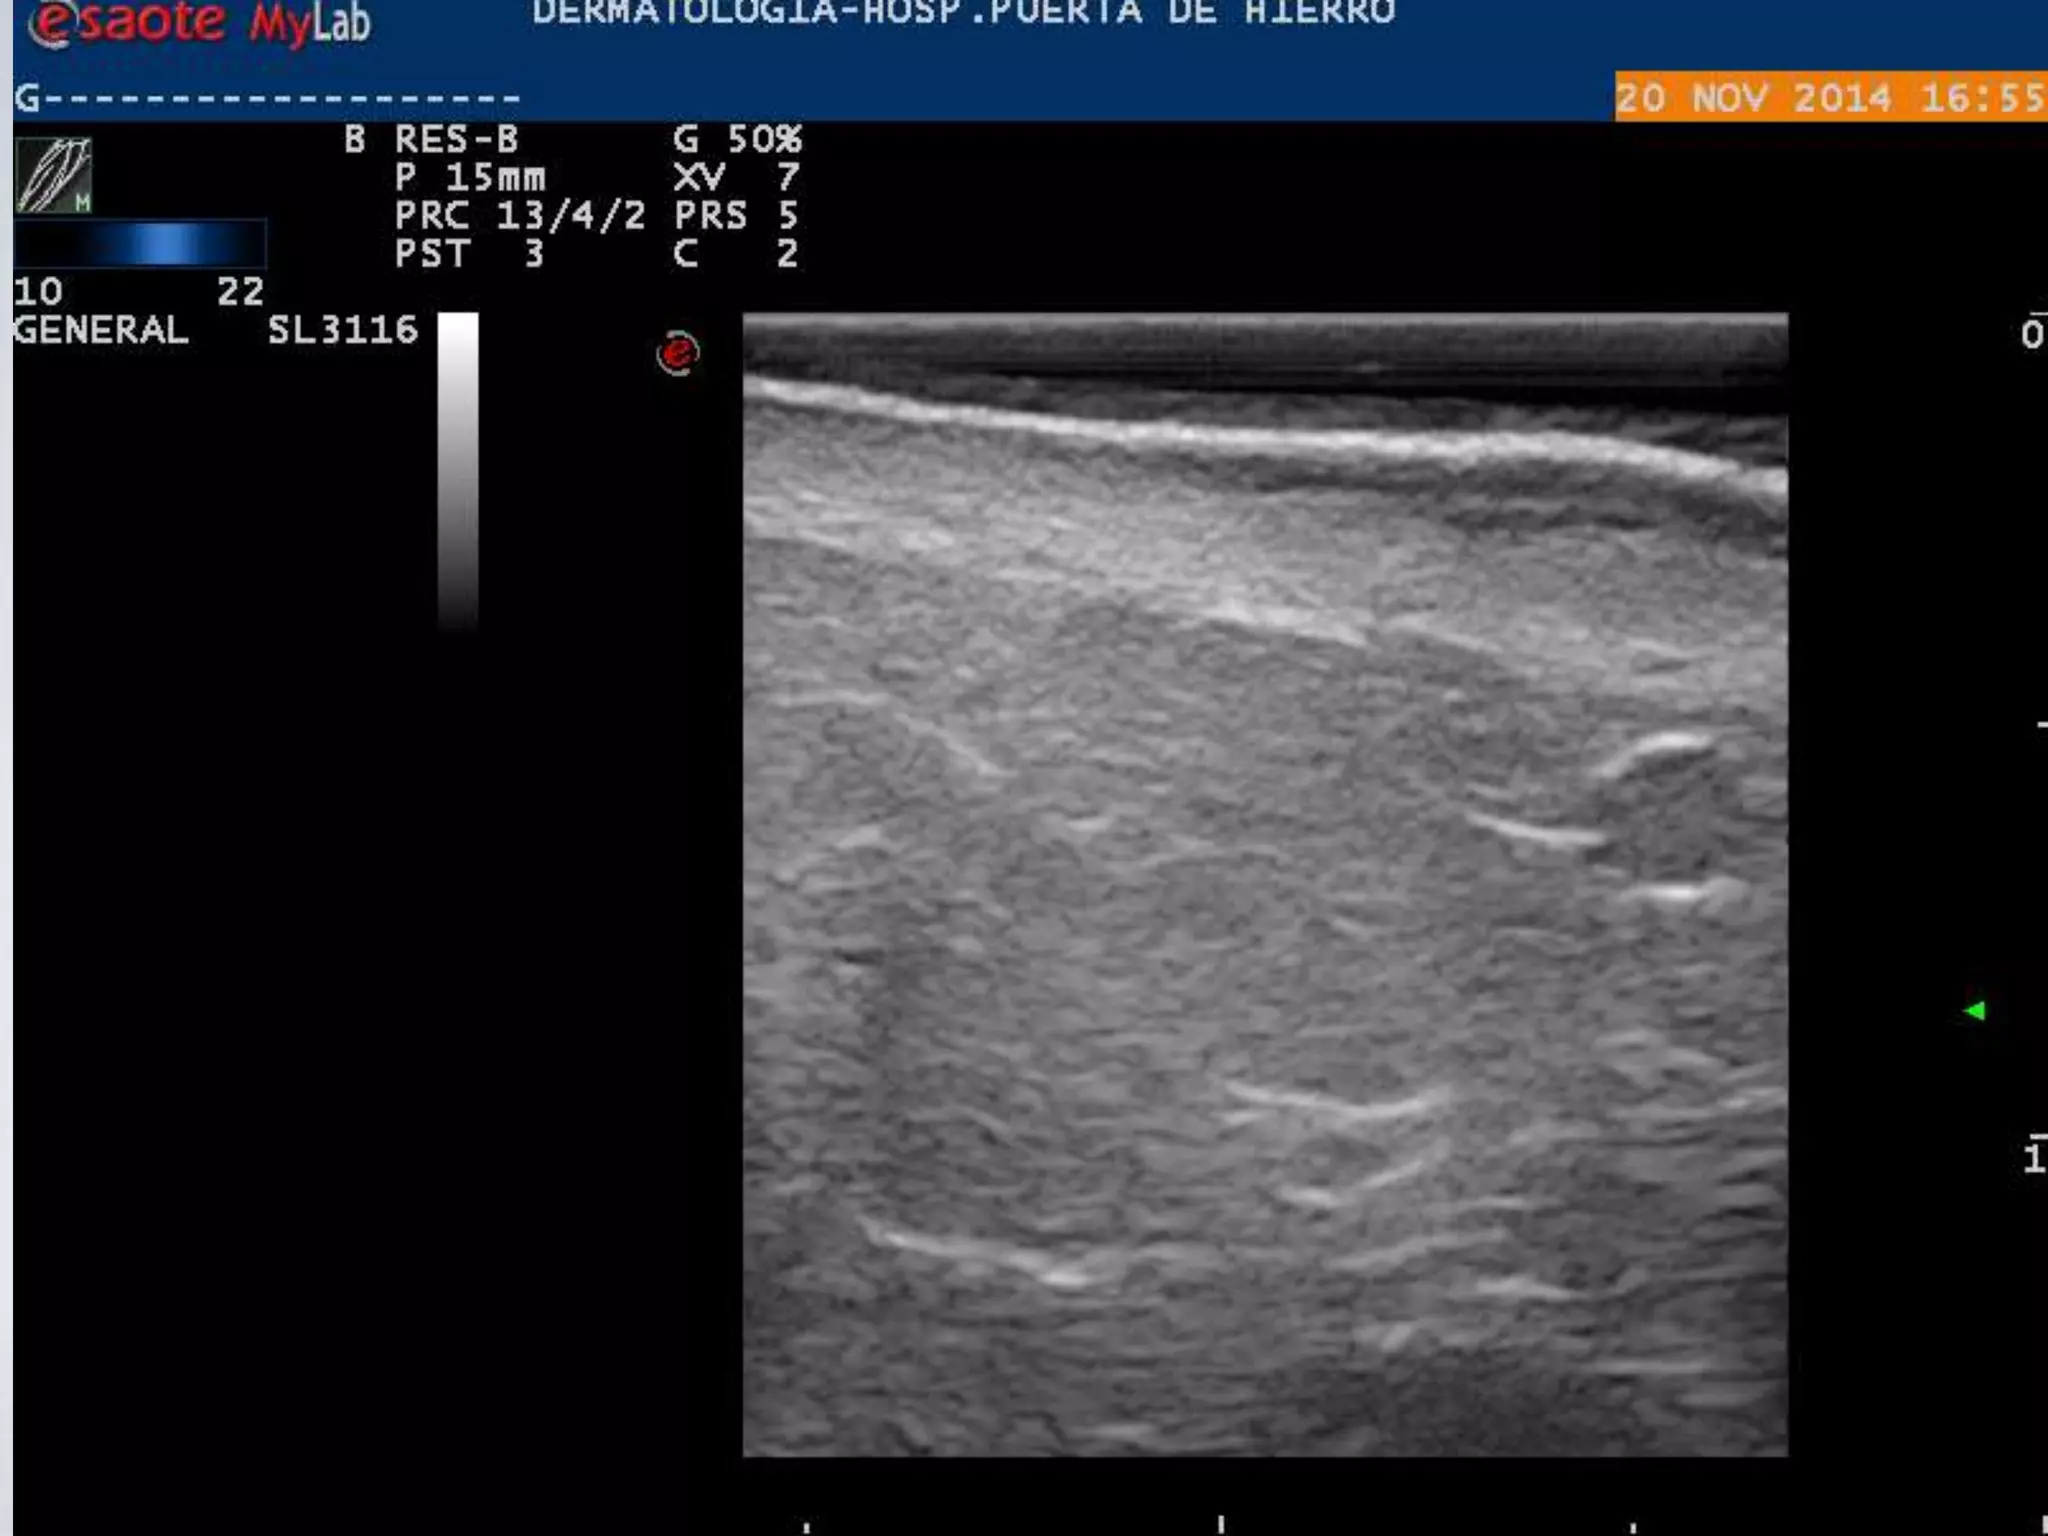

PIEL NORMAL

ECOGRAFIA

PIEL ECOGRAFICA E HISTOLOGICA

EPIDERMIS

DERMIS

TCS

FASCIA